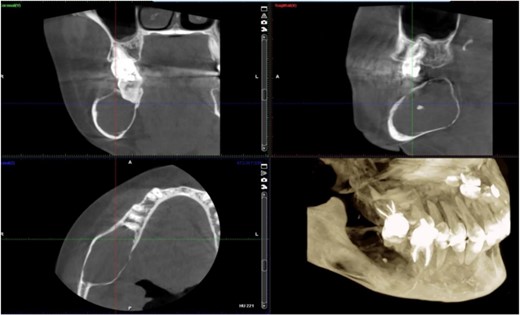

A 40-year-old woman presented with swelling on the right side of her mandible. She had completed orthodontic treatment 2 years earlier. A panoramic radiograph showed a unilocular radiolucency extending from the mandibular angle to the right first molar region (Figs 1–3).

Panoramic radiograph showing a unilocular radiolucency extending from the right mandibular angle to the right first molar region.

Panoramic radiograph highlighting the extent of the lesion from the mandibular angle to tooth #46.

Radiographic evidence showed expansile lytic lesions with sclerotic borders, consistent with IOS presentations [16]. Histology revealed Antoni A and B patterns, hyalinized Verocay bodies, and S-100 protein-positive cells, corroborating previous findings [17, 18].